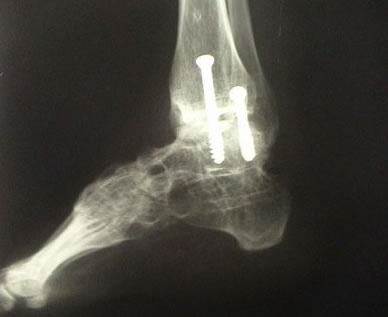

Durante a artroscopia para artrose, verificamos e tratamos várias lesões. Realizamos sinovectomia, desbridamento e retirada de corpos livres, conforme citado anteriormente. A abrasão do osso subcondral exposto e o restabelecimento dos canais de vascularização e formação de fibrocartilagem podem trazer benefícios. O desbridamento artroscópico na artrose de tornozelo é um procedimento paliativo, que visa alívio temporário da dor em pacientes que ainda apresentam alguma amplitude de movimento. Sendo assim, se houver indicação para artrodese via artroscópica, removemos toda a superfície articular do pilão tibial, domo talar e superfícies talomaleolares medial e lateral (cruentizadas) com shaver e curetas até a exposição de osso esponjoso viável. Tomamos os devidos cuidados para evitar retirada excessiva de cartilagem e osso subcondral, que podem criar deformidades em varo ou valgo. Deformidades angulares prévias podem ser corrigidas artroscopicamente ou via aberta.

Ressecamos o osteófito anterior para possibilitar a redução do domo talar na articulação do tornozelo. Após preparar a área a ser artrodesada, inserimos dois guias canulados para o drill, um lateralmente através do maléolo lateral e um medialmente, através do maléolo medial. Porém, a angulação dos guias canulados será de 30° inferior e 30° anterior, partindo dos maléolos. Utilizamos fluoroscopia para verificar a posição correta da artrodese. No plano sagital, desejamos a posição neutra de dorsiflexão e flexão plantar do tornozelo e no plano coronal o calcâneo deve estar em 5° de valgo. Finalmente, utilizando parafusos canulados de 6,5mm através do guia, concluímos a artrodese.